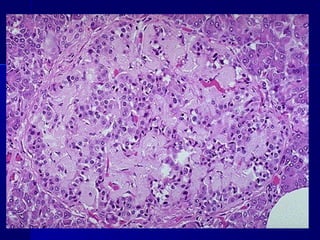

 NEFROPATÍA DIABÉTICA:NEFROPATÍA DIABÉTICA:

- Afectación glomerular da lugar a proteinuria progresi-- Afectación glomerular da lugar a proteinuria progresi-

va con IRC. Glomerolosclerosis nodular (lesiones deva con IRC. Glomerolosclerosis nodular (lesiones de

Kimmelstiel-Wilson)Kimmelstiel-Wilson)

Glomeruloesclerosis diabética